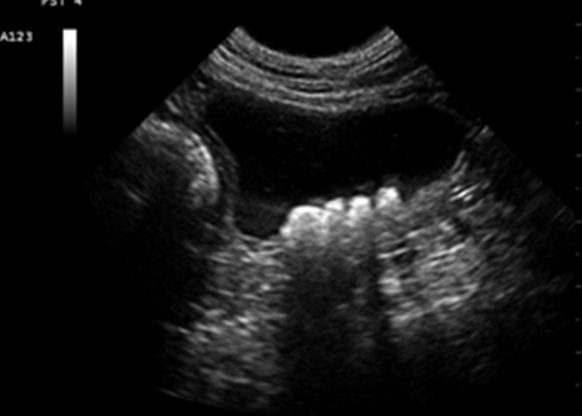

Name this pathology.

What are Bladder Stones?